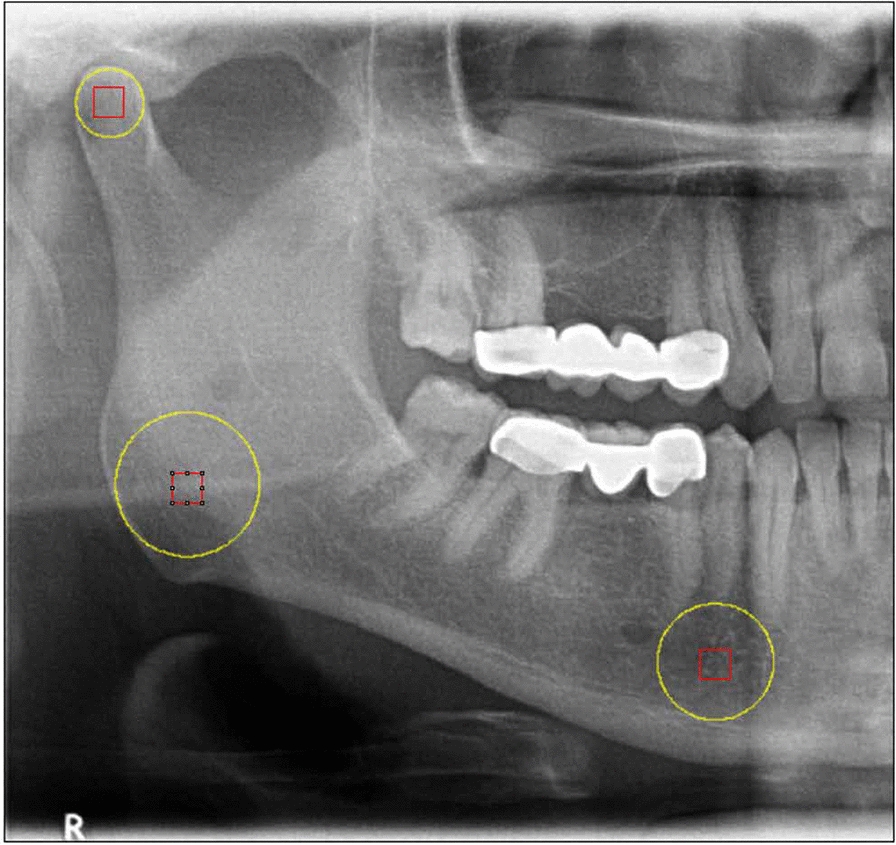

Methods: A retrospective, age- and gender-matched, 3-year longitudinal comparison was performed using 120 panoramic radiographs from 60 individuals (30 PHPT; 30 controls). Each participant contributed baseline and 3-year images (mean interval: 3.26 ± 0.13 years). Radiomorphometric indices (SI, MI, AI, PI, PMI) and FD from three standardized regions of interest (ROI1: condyle; ROI2: angle; ROI3: mental) were measured. Intra-observer reliability was excellent (ICCs 0.80-0.96). Between-group and within-group comparisons used Mann-Whitney U and Wilcoxon signed-rank tests (two-sided, p < 0.05).

Results: The antegonial index (AI) was lower in PHPT than controls at baseline (3.26 ± 0.43 vs. 3.62 ± 0.81 mm; p = 0.034) and remained lower at 3 years (3.24 ± 0.35 vs. 3.55 ± 0.43 mm; p = 0.050). Other indices (SI, MI, PI, PMI) showed no between-group differences at either timepoint and no significant within-group change (all p > 0.05). FD analysis showed a lower ROI2 (mandibular angle) value in PHPT at baseline (p = 0.050) and a significant difference at 3 years (p < 0.01); ROI1 and ROI3 did not differ between groups at either timepoint and exhibited no temporal change (all p > 0.05).